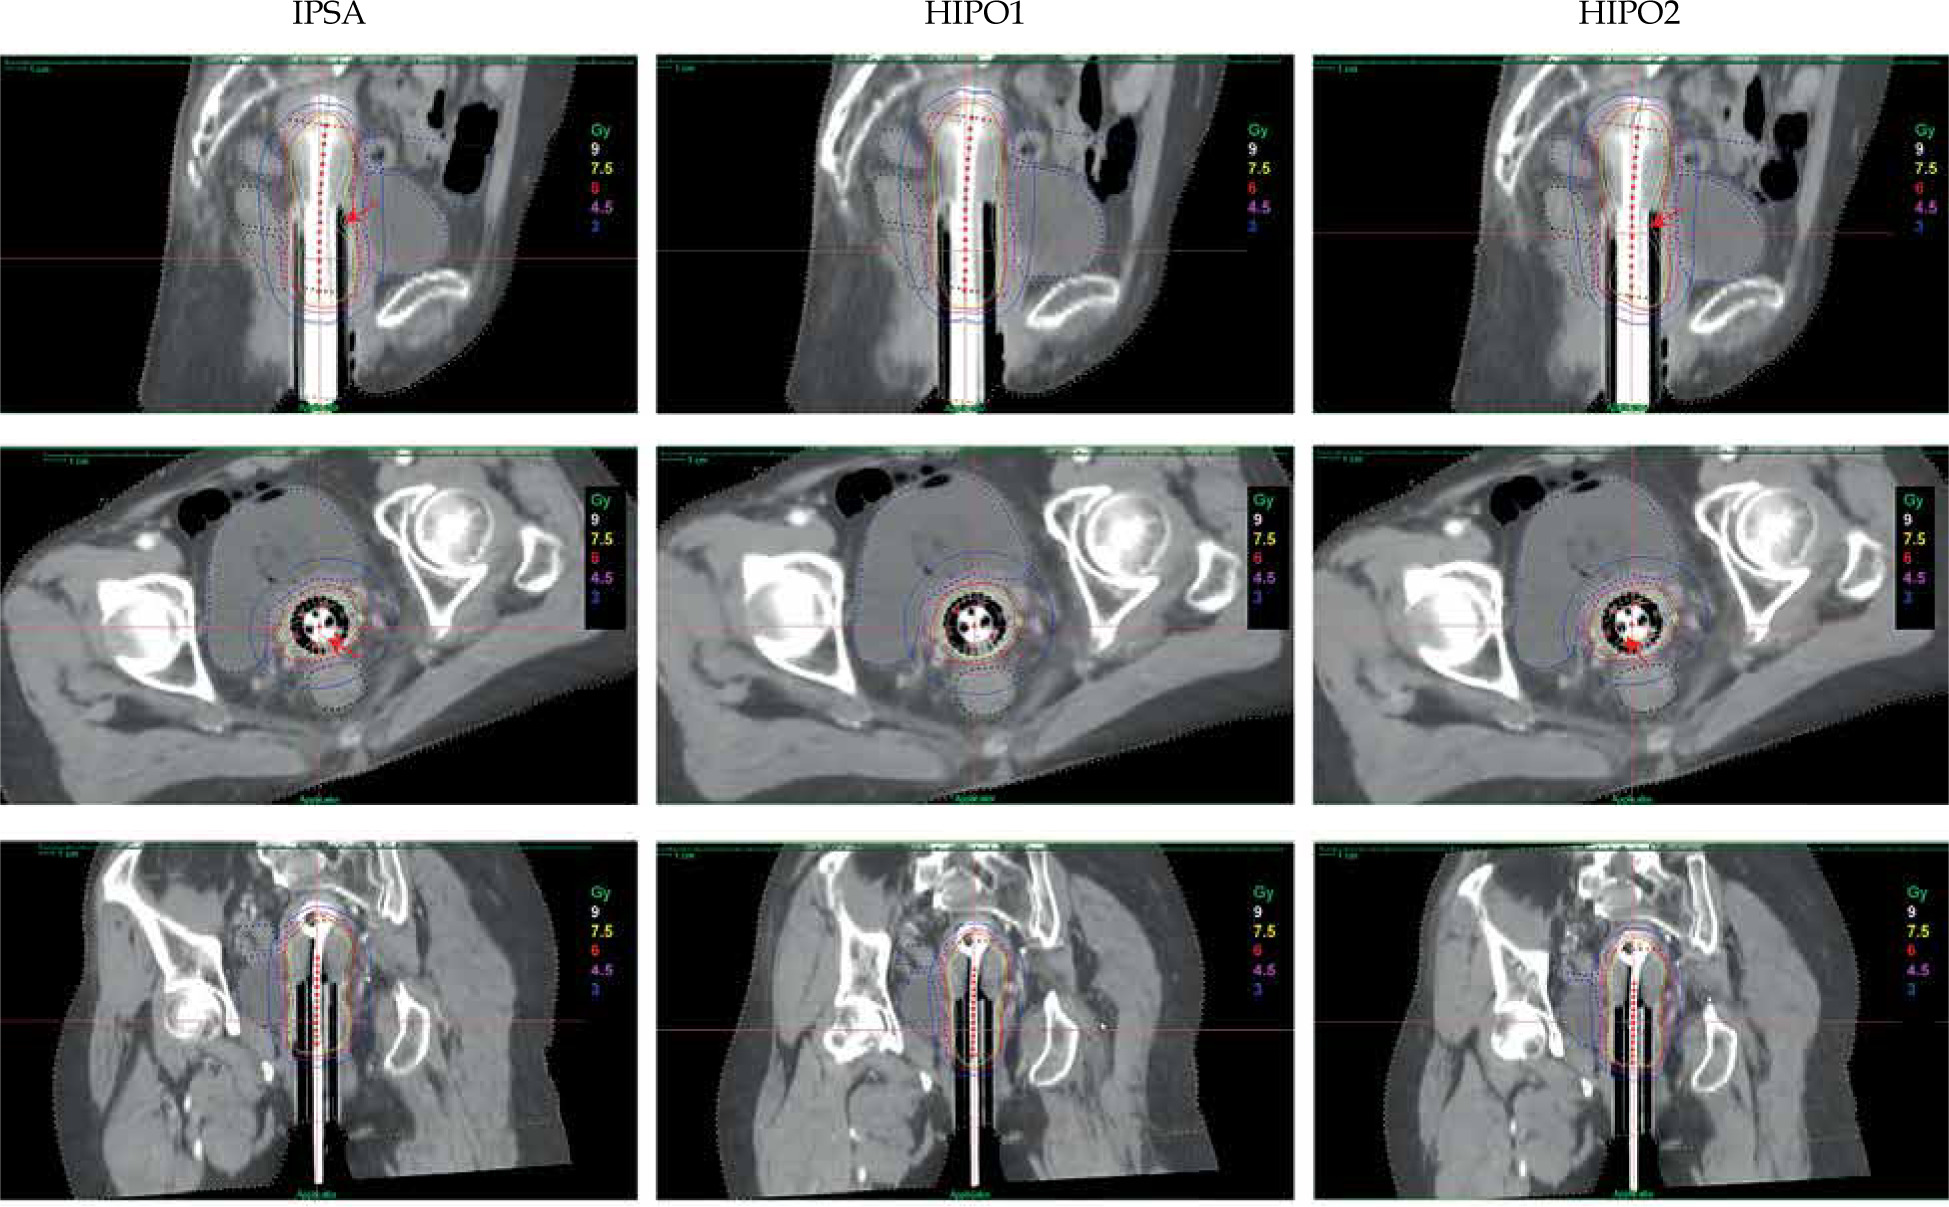

Isodose line

Figure 1 shows an image of a representative case from the patient cohort. The 9 Gy isodose line (high-dose region) of HIPO1 was smoother than that of IPSA and HIPO2, especially in the cervix region.